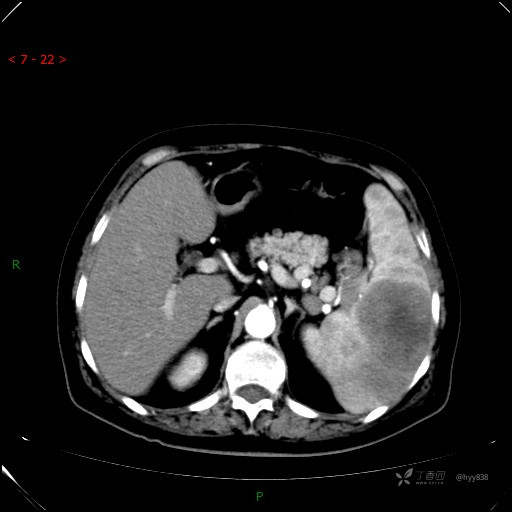

静脉期